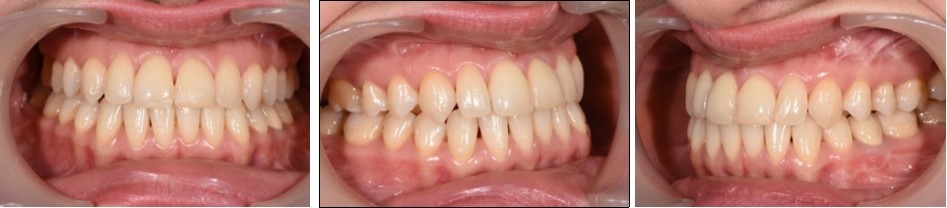

Post-treatment extraoral examination revealed that all pretreatment objectives were met. The arches were leveled and aligned, obtaining a stable occlusion with both canine and molar class I relationships. Lower incisors mainteined a normal position at the moment of debonding.

Both the mandibular deviation and the dental midline were corrected improving facial esthetics and dental occlusion. The profile of the patient dramatically improved from concave to straight, the new skeletal ralation providing better support for the upper and lower lips with no lip strain..

The total duration of the treatment was 24 months. The patient was fitted with vacuum formed retainers for the upper and lower arches and a bonded retainer from cuspid to cuspid in the lower arch. The patient was satisfied with facial esthetics, chin projection, facial profile and smile. (Figure 8), (Figure 9).